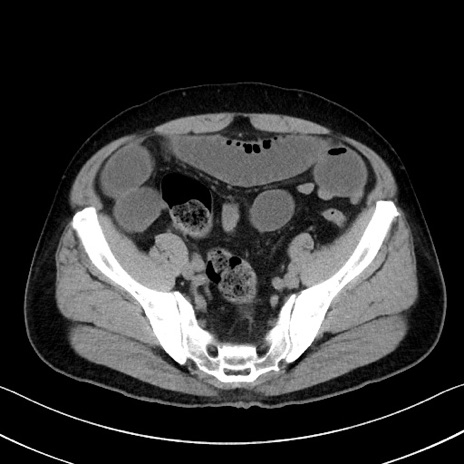

症例35(横断像)

【症例】70歳代 男性

【主訴】腹部膨満、嘔吐

【現病歴】昨日より腹部膨満感出現。本日増悪し、仙痛出現。嘔吐あり、受診。

【既往歴】糖尿病、胆摘後

【身体所見】BP 149/80mmHg、HR 74/min、BT 35.9℃、腹部:膨満、軟、圧痛なし。腸雑音減弱あり。上腹部正中切開瘢痕あり。

【データ】WBC 13500、CRP 1.72